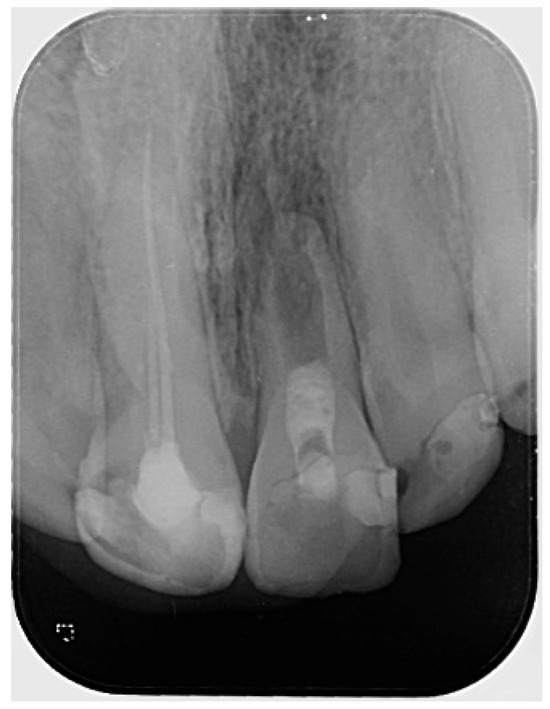

The periapical radiograph showed that tooth #21 had undergone previous endodontic treatment. A diffuse periapical radiolucency was observed surrounding the open apex. Additionally, the root appeared relatively short and exhibited thinner dentinal walls compared to the adjacent tooth #11 (Figure 1).

Figure 1.

Preoperative radiograph of tooth #21. The radiograph shows previous endodontic treatment, with the root canal filling material not extending to the full length of the canal. A diffuse radiolucency is visible around the open apex. (The mark in the lower left corner indicates the left side).